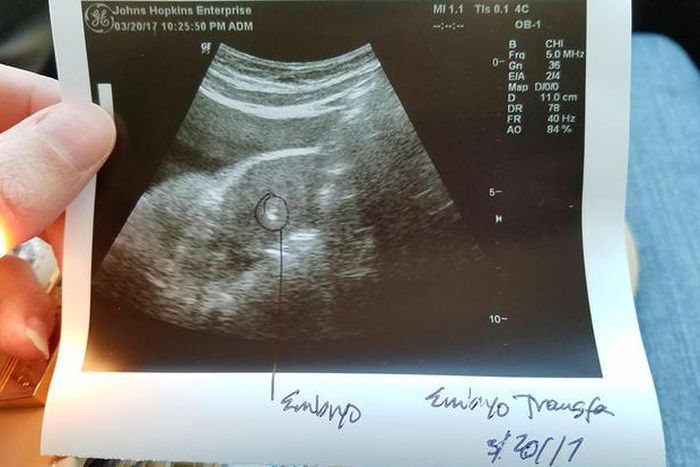

The doctor transfers one "excellent quality and high grade" embryo and tells me they'll freeze the other four embryos.

They give us a printout of the embryo they put in my body and I'm feeling hopeful.

I'm staying occupied but also taking it easy this week because I may be pregnant. I keep looking at the printout of the embryo that the clinic gave us. Our little embryo is adorable! I'm feeling excited that this may finally lead us to our baby.